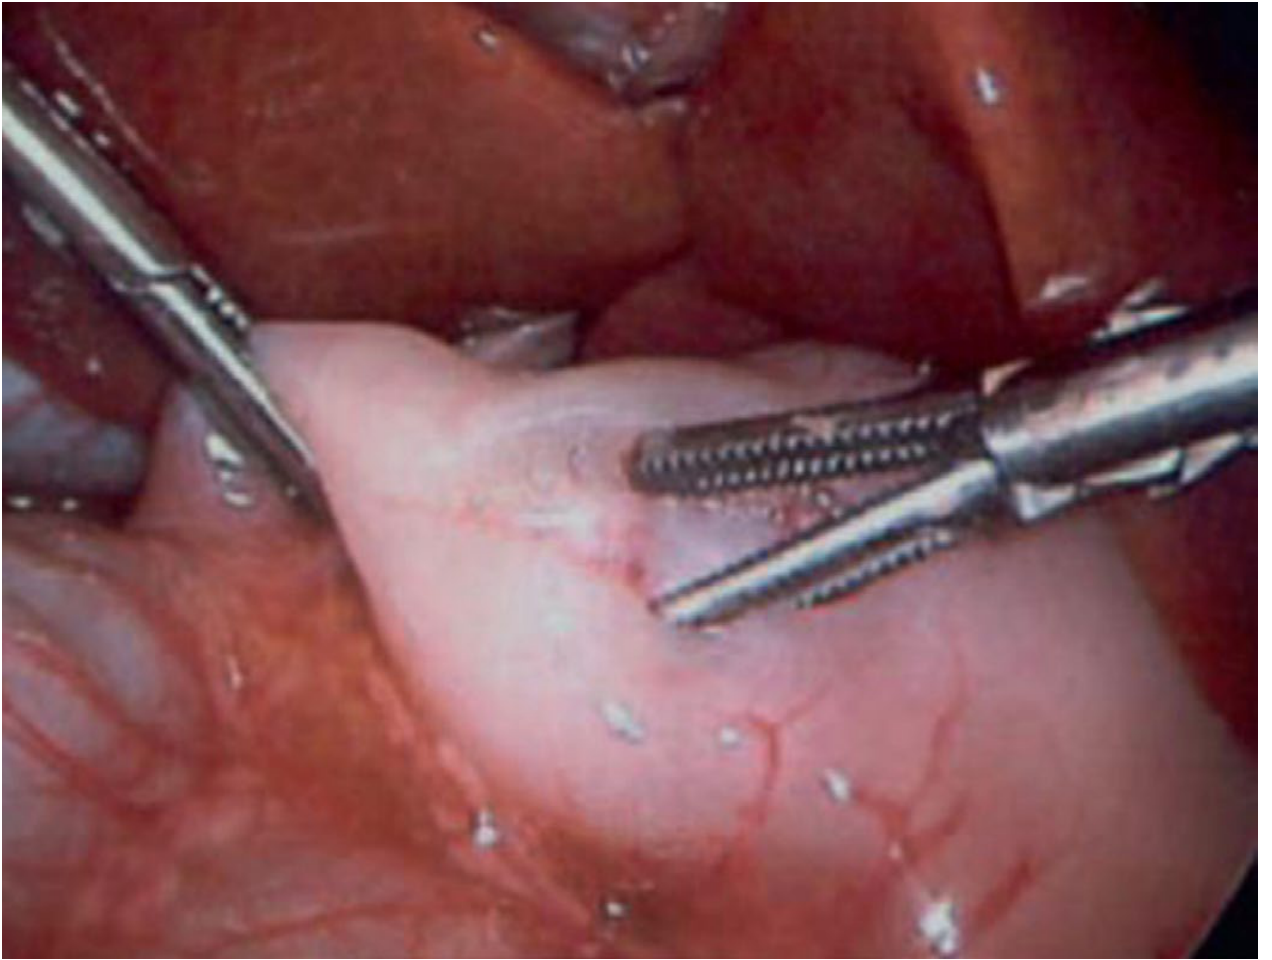

Definitive surgery — Fredet-Ramstedt Pyloromyotomy:

• Longitudinal incision through the hypertrophied pyloric muscle (serosa down to submucosa) — does not enter the mucosa

• Key endpoint: bulging mucosa throughout the length of the incision + independent wall motion of the two muscle edges

• Mucosal perforation must be excluded by injecting air via nasogastric tube

• Approaches: laparoscopic (preferred — shorter stay, lower wound infection rate) or open (umbilical or right upper quadrant transverse incision)

Laparoscopic pyloromyotomy: retractable blade incises thickened pyloric muscle; spreader widens the myotomy until intact mucosal bulging and independent wall motion are confirmed

Laparoscopic Fredet-Ramstedt pyloromyotomy. — Sabiston Textbook of Surgery